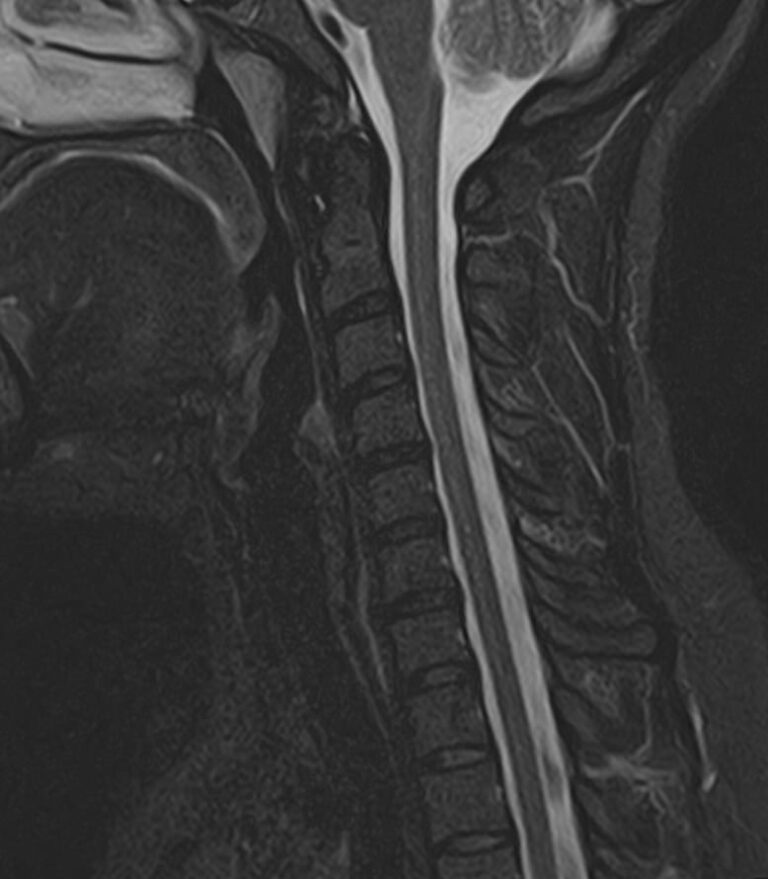

Шейный отдел позвоночника — это самый подвижный сегмент позвоночного столба, который испытывает повышенные нагрузки, подвержен травмам и развитию различных заболеваний. В эту анатомическую область входит 7 верхних позвонков, спинной мозг с отходящими от него нервными корешками, а также проходят крупные сосуды, кровоснабжающие головной мозг. К ним относятся плечеголовной ствол, сонные и позвоночные артерии.

Для того, чтобы оценить состояние шейных позвонков с прилегающими тканями и одновременно визуализировать крупные сосуды шеи, в нашей клинике выполняется комплексное обследование, включающее два протокола: МРТ шейного отдела позвоночника и МР-ангиографию шеи.

В клинике «Доступная медицина» комплексное обследование шейного отдела позвоночника одновременно с МР-ангиографией шеи проводится на новейшем высокопольном томографе экспертного уровня TOSHIBA VANTAGE TITAN 1,5 Тесла, который производит послойное сканирование исследуемой зоны в разных плоскостях, затем при помощи компьютерных программ преобразует полученные данные в трехмерные изображения шейного отдела позвоночника и кровеносной системы, что позволяет проводить точную диагностику и назначать пациенту своевременное лечение.

Данное комплексное исследование позволяет проводить диагностику следующих патологических состояний:

• дегенеративно-дистрофические заболевания шейного отдела позвоночника (межпозвонковые грыжи, протрузии, остеохондроз, спондилоартроз, спондилез, унковертебральный артроз, сколиоз, усиленный или выпрямленный лордоз как нарушение статической функции позвоночника);

• травмы позвоночника, спинного мозга, связочного аппарата, близлежащих мягких тканей;

• опухоли спинного мозга, костей, нервных корешков или мягких тканей, окружающих позвоночник;

• инфекционные и воспалительные заболевания позвоночника и спинного мозга;

• демиелинизирующие заболевания спинного мозга;

• аномалии развития позвоночника;